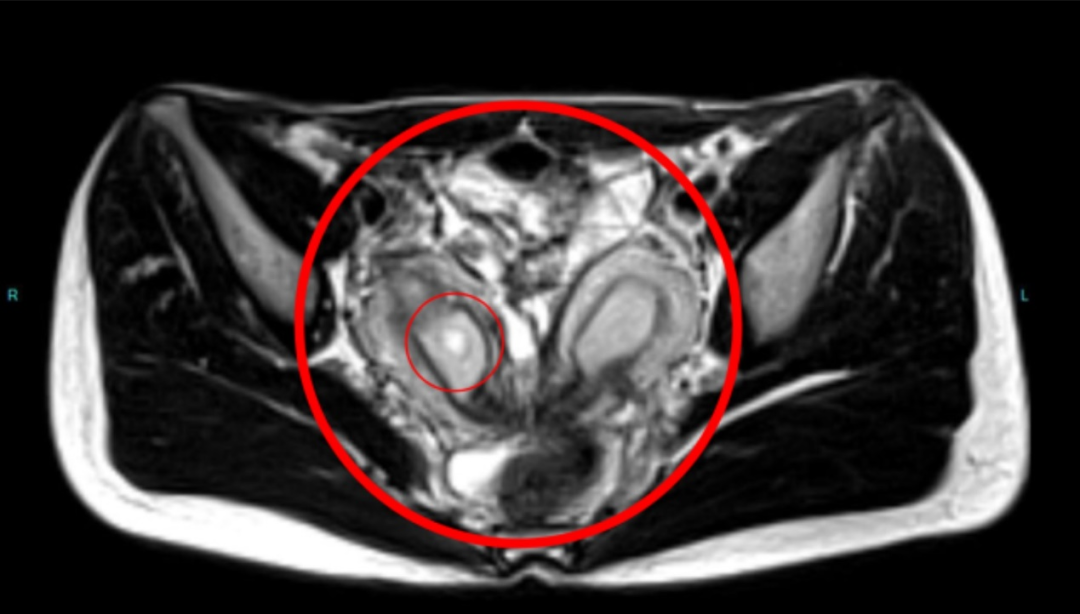

当超声结果不够清晰或需要更精细解剖评估时,医生可建议行盆腔MRI检查。

MRI优势在于软组织对比度高,可精确显示子宫外形和宫腔形态,帮助鉴别双子宫、双角子宫与纵隔子宫等不同类型,有利于制定管理策略。